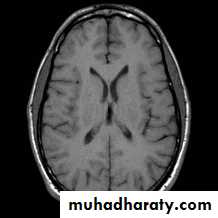

T1 WEIGHTING

A short TR and short TE will result in a T1 weighted imageExcellent for demonstrating anatomy

Image formationThe image will depend on T1,T2, and amount of proton within the tissue (spin density ) .

The fatty tissues is loosing energy quickly so it will re appear its longitudinal vector rapidly ( high T1 signal)

Water loosing energy and synchronization slowly so it will appear bright at T2 and black on T1

Solid material will not give a signal on t1 and t2 (signal void )

T1-, -, and T2-weighted images

-weightedT2-weighted

T1-weighted